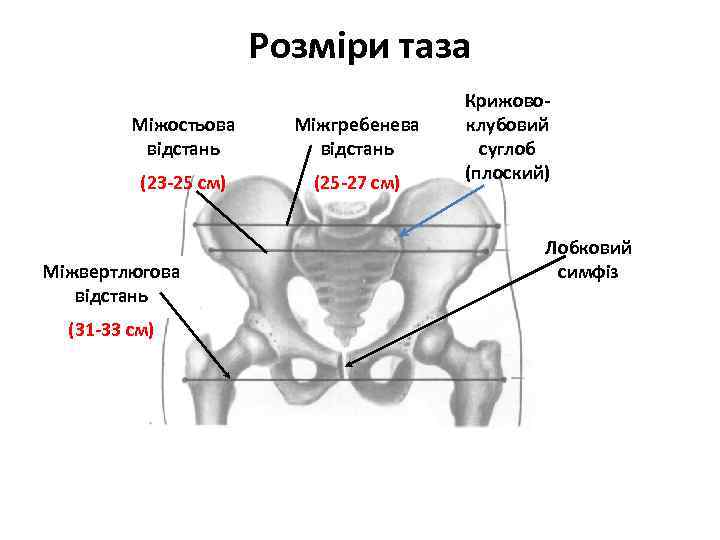

Розміри таза Міжостьова відстань Міжгребенева відстань (23 -25 см) (25 -27 см) Міжвертлюгова відстань (31 -33 см) Крижовоклубовий суглоб (плоский) Лобковий симфіз